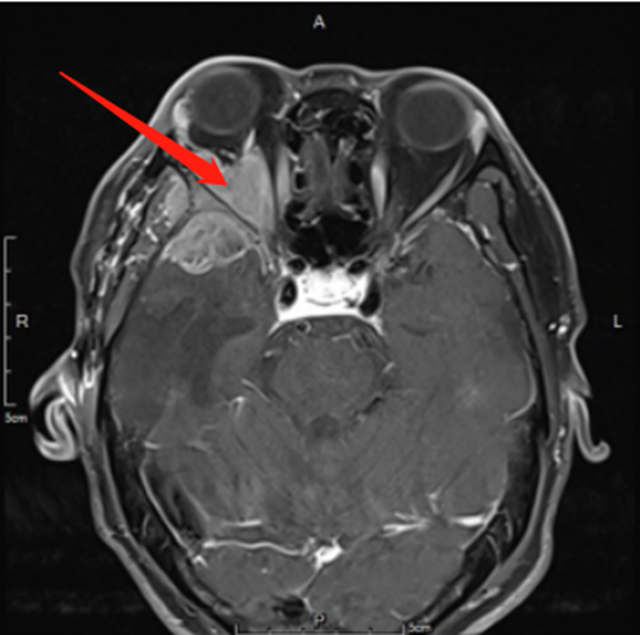

59岁的胡大叔,一年前因为左肺小细胞癌,到附近医院做了“单孔胸腔镜左侧胸腔粘连松解术+左肺上叶结节切除术”,术后又进行了多次放疗,恢复还不错。  2023年5月底,胡大叔出现了右眼胀痛、视物模糊、右眼球外突的症状,便来到了西南医科大学附属...